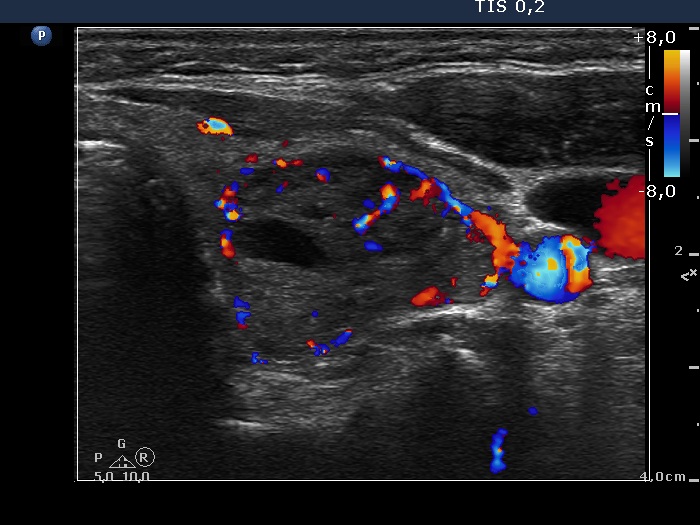

Study on 100 consecutive patients with thyroid nodule - case 024 (ultrasonographic picture 13)

Left lobe, transverse scan, color Doppler mode - after aspiration of 9 mL brown fluid. The nodule displays both intranodular and perinodular blood flow.